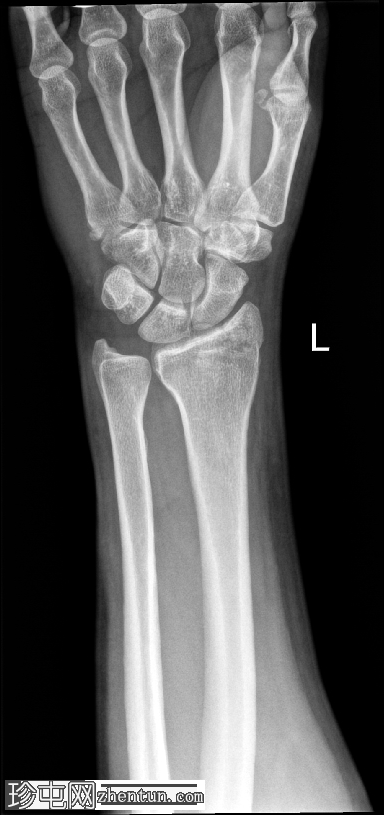

正面

桡骨茎突骨折,符合Chauffeur骨折的诊断。骨折线斜向延伸至桡骨远端外侧,并累及桡骨茎突。

桡腕关节外观吻合;无明显关节面塌陷。舟骨和其他腕骨外观完整,腕骨列排列正常。尺骨远端和尺骨茎突完整。

旋前方肌脂肪垫抬高,与相关软组织肿胀和骨折相符。

本例中,桡骨茎突骨折块移位轻微,腕骨排列保持完整。可见旋前方肌脂肪垫隆起,提示与骨折下部相关的软组织水肿。